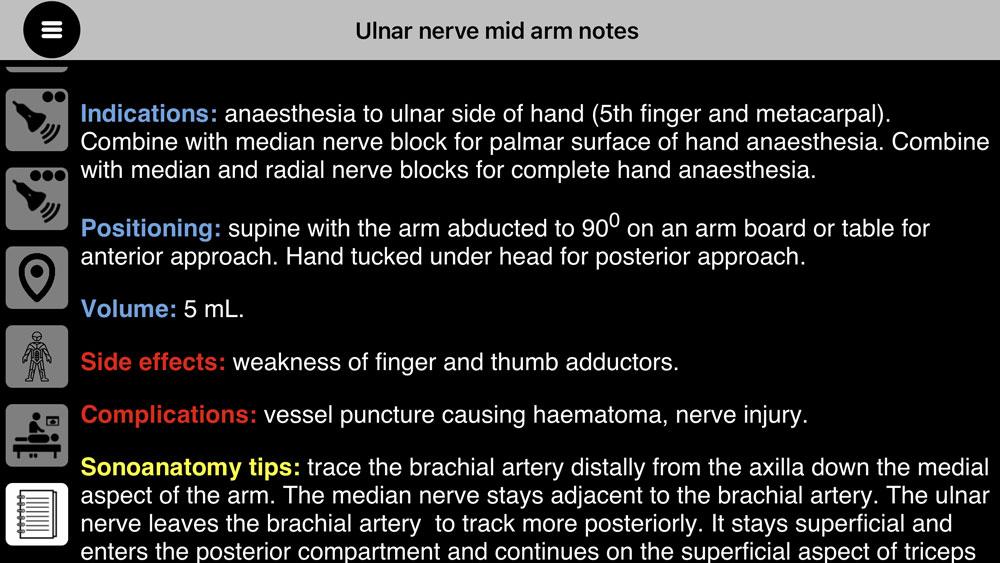

- 提供带有声解剖提示的块注释和实用技巧来自经验丰富的临床医生的指导,这对学习者来说非常宝贵。

- 提供带有声解剖提示的块注释和实用技巧来自经验丰富的临床医生的指导,这对学习者来说非常宝贵。

- 记录经验丰富的临床医生的提示。